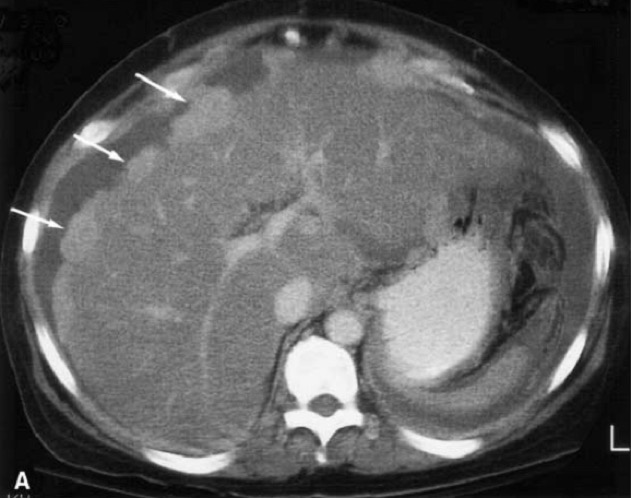

3. Solid Organs – Liver, Spleen, Kidneys

- Focal hypoattenuating masses

- Increase in size